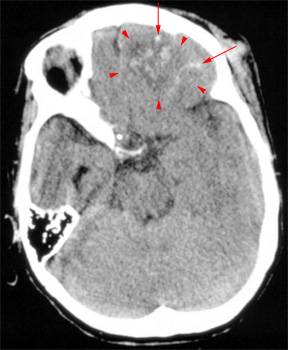

On CT, cerebral contusion appears as an ill-defined hypodense area mixed

with foci of hemorrhage. Adjacent subarachnoid hemorrhage is common. After

24-48 hours, hemorrhagic transformation or coalescence of petechial hemorrhages

into a rounded hematoma is common.